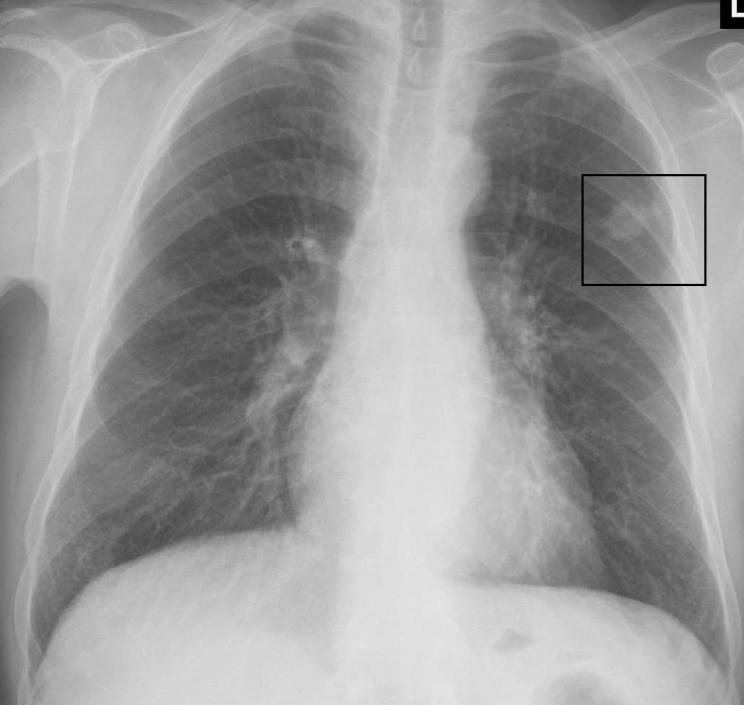

La localizzazione è soprattutto polmonare, quindi si trasmette in particolare per via aerea, ma non è da escludere che possa trovarsi anche nelle feci di un animale infetto e che possa essere mangiato o leccato da un altro animale, principalmente se a trasmetterlo sono gli uccelli.

Come dicevamo prima, i micobatteri sono resistentissimi. Una volta che vengono assunti ingerendoli o respirandoli si localizzano, rispettivamente, nel polmone o nell'intestino. Qui vengono subito riconosciuti dal sistema immunitario del cane o del gatto, le cui cellule preposte (i macrofagi) agiscono in questo modo: mangiano e digeriscono il batterio, distruggendolo. O almeno ci provano. Perché se per la maggior parte dei batteri questo processo è sufficiente, i micobatteri riescono a resistere alla digestione.

Quando l'organismo si rende conto di poter far poco in questa situazione, crea delle vere e proprie "barricate" per far sì che il batterio rimanga confinato in un certo punto, barricate che crescono sempre di più (e divengono dei tubercoli, da qui il nome tubercolosi) perché proprio, contro i micobatteri, non c'è nulla da fare.

I noduli crescono sempre di più, causando problemi alla digestione e alla respirazione, perché tolgono spazio alle normali operazioni vitali. A volte poi si spezzano (soprattutto a causa dei colpi di tosse), e da un nodulo se ne formano due, che continuano a crescere, e così via, fin quando la situazione diventa intollerabile.

Da quanto abbiamo appena detto, avrete capito che curare la tubercolosi è molto difficile. Ci sono degli antibiotici, che però sono utili se ci rendiamo conto (grazie a test specifici) che è presente l'infezione. Il problema è che a volte ci vogliono anni perché sintomi come la tosse persistente compaiano, e questo rende visibile la malattia quando ormai è troppo tardi.